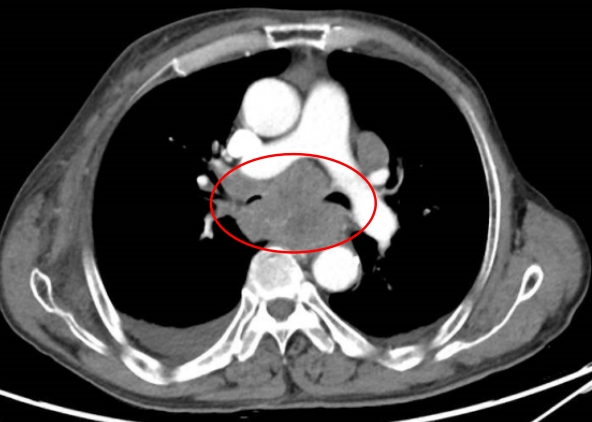

62岁的陈阿姨,因持续一个月的胸闷和呼吸困难入院。胸部CT扫描显示,她的右侧锁骨区、纵隔和双肺门有多发性肿大的淋巴结,这可能是淋巴瘤或结节病的迹象。

诊断结果:肺结节病